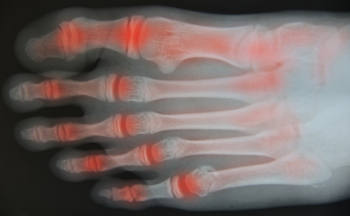

Toe Arthritis

If you are experiencing pain and discomfort in your big toe, you may have a foot condition that is known as toe arthritis. It may be caused by wearing shoes that are too tight and may not have adequate room for the toes to move about in. One of the first signs that may be indicative of toe arthritis may be pain that is felt in the toes. Many people feel stiffness in the toes, and this may be a result of the diminished cartilage that is located between the joints, in addition to obvious redness and swelling of the toes and surrounding area. If you are afflicted with this condition, it may be difficult to perform daily activities that may include walking or standing for extended periods of time. If you are experiencing arthritis in your feet or toes, it is suggested to speak with a podiatrist who can advise you on correct treatment options.

If you are experiencing pain and discomfort in your big toe, you may have a foot condition that is known as toe arthritis. It may be caused by wearing shoes that are too tight and may not have adequate room for the toes to move about in. One of the first signs that may be indicative of toe arthritis may be pain that is felt in the toes. Many people feel stiffness in the toes, and this may be a result of the diminished cartilage that is located between the joints, in addition to obvious redness and swelling of the toes and surrounding area. If you are afflicted with this condition, it may be difficult to perform daily activities that may include walking or standing for extended periods of time. If you are experiencing arthritis in your feet or toes, it is suggested to speak with a podiatrist who can advise you on correct treatment options.

Arthritis can be a difficult condition to live with. If you are seeking treatment, contact Dr. Michael T. Hames from Florence Foot Center. Our doctor can provide the care you need to keep you pain-free and on your feet.

Arthritic Foot Care

Arthritis is a term that is commonly used to describe joint pain. The condition itself can occur to anyone of any age, race, or gender, and there are over 100 types of it. Nevertheless, arthritis is more commonly found in women compared to men, and it is also more prevalent in those who are overweight. The causes of arthritis vary depending on which type of arthritis you have. Osteoarthritis for example, is often caused by injury, while rheumatoid arthritis is caused by a misdirected immune system.

Symptoms

- Swelling

- Pain

- Stiffness

- Decreased Range of Motion

Arthritic symptoms range in severity, and they may come and go. Some symptoms stay the same for several years but could potentially get worse with time. Severe cases of arthritis can prevent its sufferers from performing daily activities and make walking difficult.

Risk Factors

- Occupation – Occupations requiring repetitive knee movements have been linked to osteoarthritis

- Obesity – Excess weight can contribute to osteoarthritis development

- Infection – Microbial agents can infect the joints and trigger arthritis

- Joint Injuries – Damage to joints may lead to osteoarthritis

- Age – Risk increases with age

- Gender –Most types are more common in women

- Genetics – Arthritis can be hereditary

If you suspect your arthritis is affecting your feet, it is crucial that you see a podiatrist immediately. Your doctor will be able to address your specific case and help you decide which treatment method is best for you.